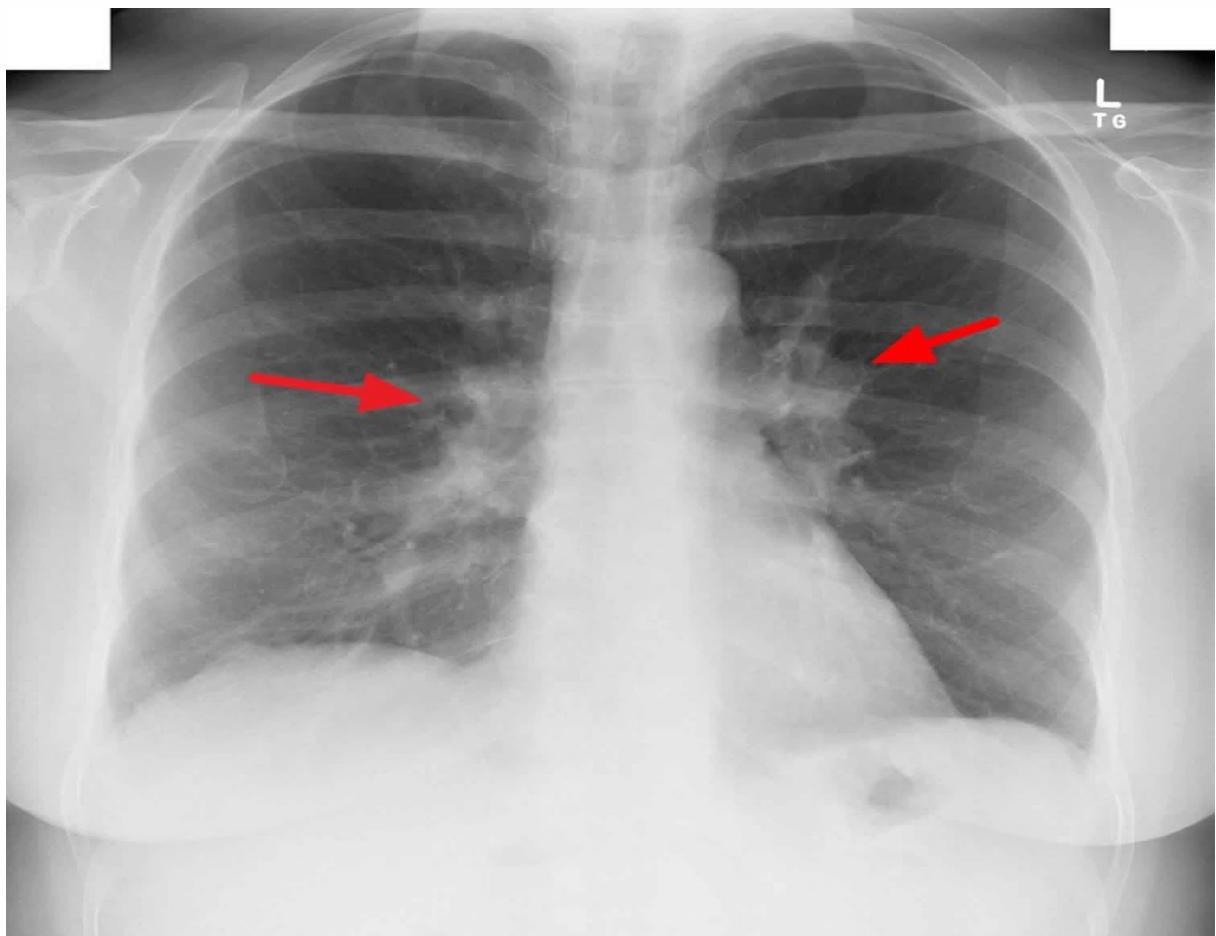

Chest x-ray showing diffuse bilateral opacities.

3. Miliary Tuberculosis

- Definition: Widespread hematogenous dissemination to multiple organs; lesions resemble millet seeds.

- Risk: Young/immunocompromised patients.

- Presentation: Fever, general malaise, weight loss, lymphadenopathy, night sweats, hepatosplenomegaly, diffuse bilateral pneumonitis.